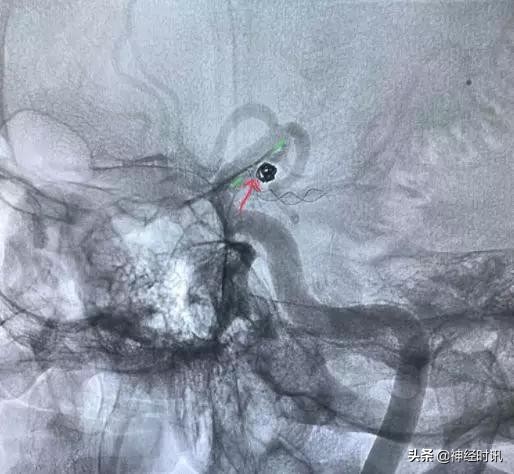

点击图片可查看大图详情

换一个角度看:绿色虚线代表颈内动脉边缘,红箭头为支架的显影丝,是不是正好平齐呢?